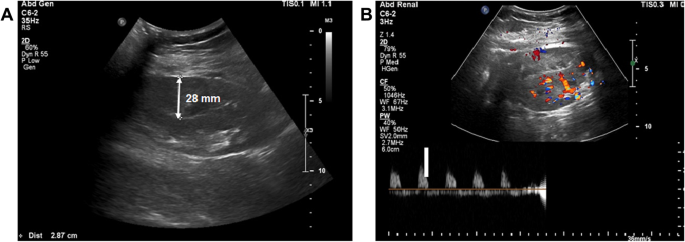

The patient's urinary output was maintained at an average of 100 cc per hour. His initial vital signs were as follows: blood pressure, 145/85 mmHg; heart rate, 92 beats/min; respiratory rate, 20 breaths/min; and body temperature, 36.5 °C. They remained stable during the first 6 h after surgery. On postoperative day (POD) 1, His medication included immunosuppression such as tacrolimus, mycophenolic acid, and methylprednisolone. He did not take any anti-coagulant medications. The patient's urine volume decreased to an average of 29 cc per hour. Saline infusion and diuretic treatment were performed to increase urinary output but no change in urine volume was observed. His serum creatinine level was 6.6 mg/dL preoperatively and 5.2 mg/dL on POD 1 (Fig. 1). No BP surge occurred on POD 1. Doppler USG showed no evidence of hydronephrosis but the renal cortex was compressed by a 28 mm deep SH (Fig. 2A). USG did not reveal evidence of rejection, renal vein thrombosis, or anastomotic stenosis in the graft artery or vein. The resistive index (RI) increased to 0.98–1 and diastolic flow reversal was observed (Fig. 2B).

Fig. 2

Doppler USG showing 28 mm in depth hematoma (A) and diastolic flow reversal (resistive index = 0.9–1) (B)

Acute pain over the allograft, uncontrolled hypertension despite appropriate medicines, and a reduction of urinary output are useful signs in the diagnosis of early stage PK [1]. Other important findings are SH and an elevated RI on Doppler USG [1, 12]. Our patient could not sense graft pain as he received a continuous intravenous infusion of narcotic analgesics immediately after allograft surgery. Hypertension was well-controlled with intravenous anti-hypertensive medicines. PK was suspected based on the sudden decrease in urinary output between 6 h and 48 h post-transplantation, the absence of a decrease in the serum creatinine level, and the detection of a 28 mm deep SH via Doppler USG, routinely performed in renal transplant patients on POD 1. Although when the subcapsular bleeding started was unknown, a hemodynamic change was not apparent until 6 h after surgery.